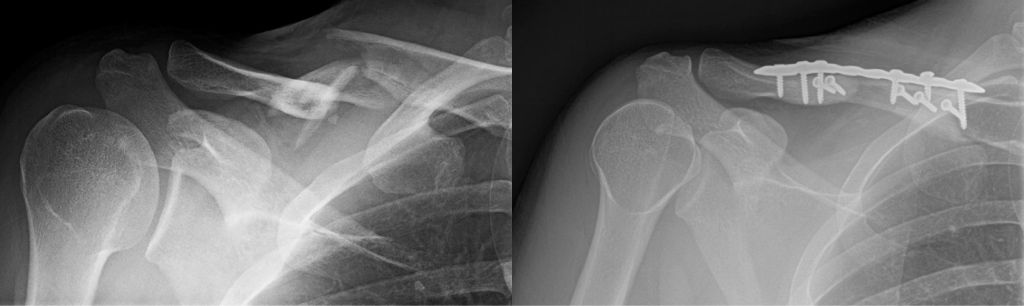

A direct fall on the shoulder can cause a "shoulder separation" or acromioclavicular (AC) joint sprain. This injury is usually sports related. Some separations happen in car accidents or falls. This is not the same as a shoulder dislocation, which occurs at the large joint where the arm attaches to the shoulder, although the two may appear to be the same.

The shoulder separation, or acromioclavicular (AC) dislocation, is an injury to the junction between the collarbone and the shoulder. It is usually a soft-tissue or ligament injury but may include a fracture (broken bone).

High grade sprains can result in elevation of the distal end of the clavicle resulting in a bump or prominence. These are usually treated without surgery. If significant displacement or pain persists after non-operative treatment, surgical repair can be performed. Acute injuries can be treated with plating or other fixation methods, whereas chronic tears require ligament reconstruction.

Shoulder radiographs demonstrating a "shoulder separation" or acromioclavicular sprain ("AC sprain"), with the clavicle end elevated away from the acromion (left image), and repair with open reduction internal fixation (right image).